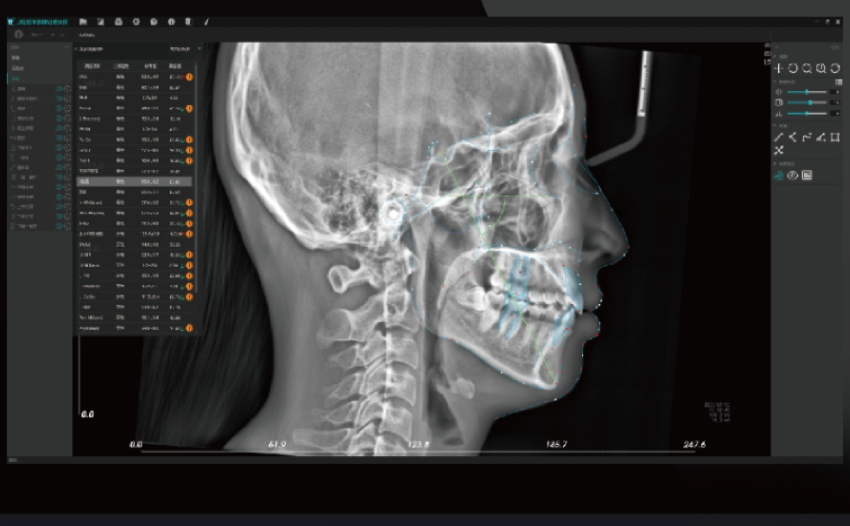

Sistema Ortodôntico Inteligente

Traçado Automático de Pontos de Referência

disponibiliza 68 pontos de referência e 192 itens de medição.

Suporte a Métodos de Análise Profissional:

auxilia os clínicos na análise quantitativa e na simulação diagnóstica.

Análise Inteligente Local:

funciona offline, sem necessidade de ligação à internet.